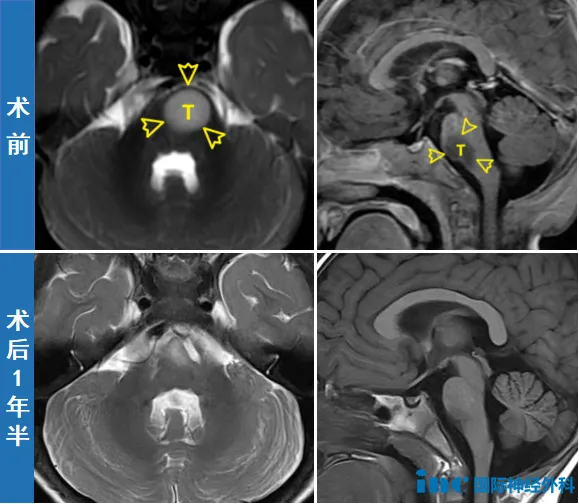

巴教授國內(nèi)最小患者 | 11月齡腦干膠質(zhì)瘤開顱術(shù)后1年半:“非常活躍,發(fā)育很好!”

兩個月后,11個月大的新新成為巴教授示范手術(shù)中年齡最小的患者,但手術(shù)的難度卻遠(yuǎn)超其他。位于腦干關(guān)鍵區(qū)域的腫瘤、與神經(jīng)纖維危險的關(guān)系、僅10kg的體重、極低的血容量和耐失血能力、極高的休克與麻醉風(fēng)險……都讓鐘女士一家心懸一線。

影像

03成功規(guī)避風(fēng)險,寶寶順利手術(shù)

實際上,新新的手術(shù)除了因年齡小、體重輕所導(dǎo)致的血量少、耐失血能力弱、麻醉和休克風(fēng)險高之外,還存在因腫瘤位置特殊所導(dǎo)致的另一大風(fēng)險——由于腫瘤位于腦干,且與神經(jīng)及運動纖維關(guān)系緊密,因此術(shù)中有可能心跳驟停,或因損傷第六顱神經(jīng)及運動纖維而產(chǎn)生并發(fā)癥。

因此,此次手術(shù)的目標(biāo)是盡可能多的切除腫瘤,與此同時保留功能,這令看重孩子未來生活質(zhì)量的鐘女士如釋重負(fù)。

很快,手術(shù)開始。盡管術(shù)中巴教授發(fā)現(xiàn)腫瘤與周圍正常組織的邊界極其模煳,幾乎無法分辨,但憑借著教授數(shù)十年如一日的熟練操作和先進(jìn)設(shè)備的保駕護航,最終手術(shù)順利,達(dá)到滿意的切除,更未損傷孩子的神經(jīng)功能。